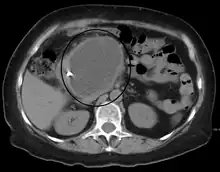

A pancreatic pseudocyst as seen on CT | |

A pancreatic pseudocyst is a circumscribed collection of fluid rich in pancreatic enzymes, blood, and non-necrotic tissue, typically located in the lesser sac of the abdomen. Pancreatic pseudocysts are usually complications of pancreatitis,[5] although in children they frequently occur following abdominal trauma. Pancreatic pseudocysts account for approximately 75% of all pancreatic masses.[6]